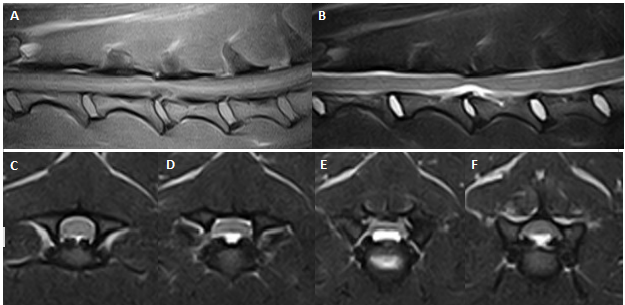

Art685_Fig9